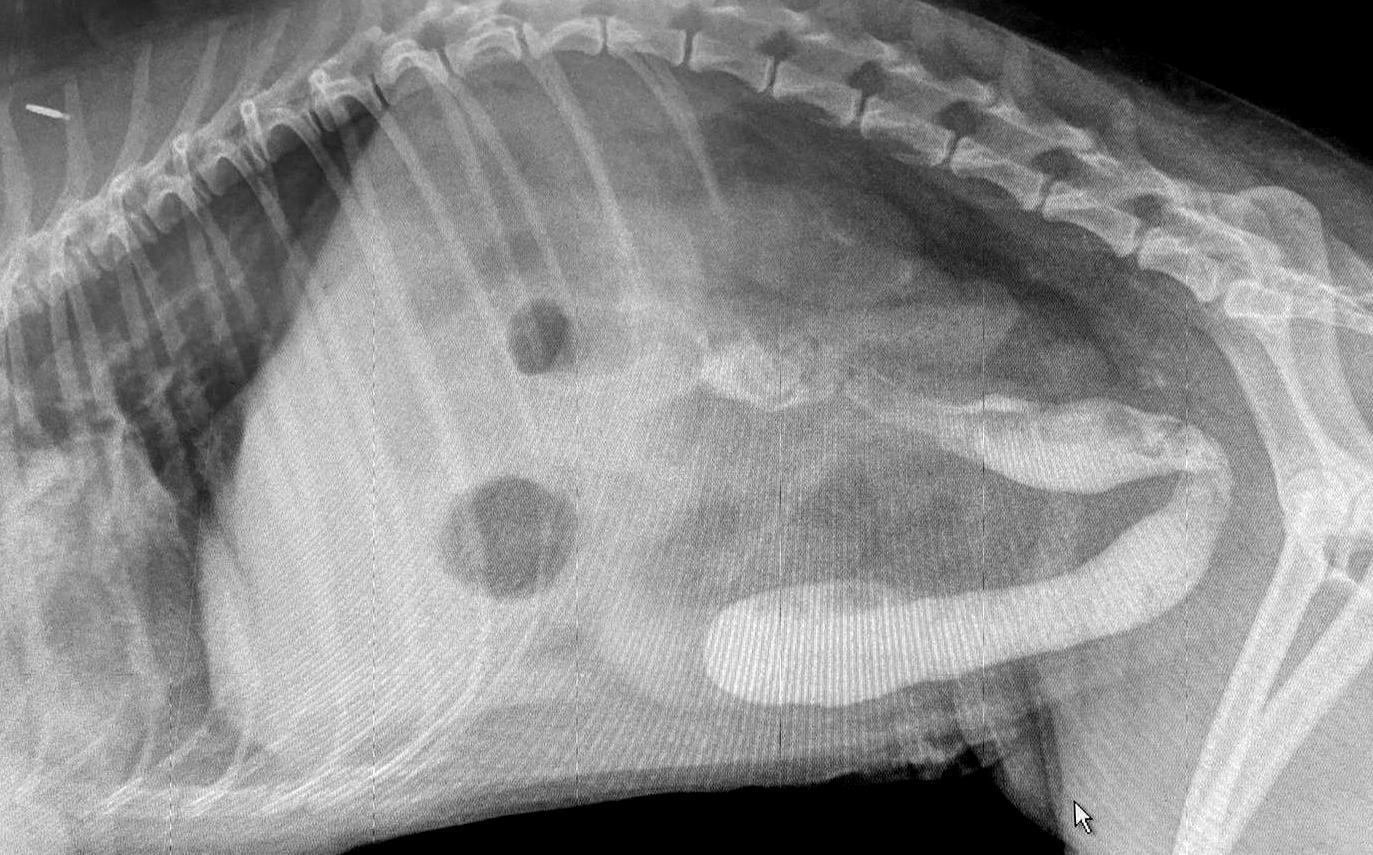

From www.diagnosticmindset.com

The reason for the haemorrhagic gastroenteritis in this dog Dog Gastroenteritis Reddit Gastroenteritis in dogs is a common condition that typically involves diarrhea and may be accompanied by vomiting. My dog began having symptoms of what my vet thought is gastroenteritis two saturdays ago when she began vomiting and having diarrhea and it. Our 14 month old female labrador retriever/german shepherd mix has had a long week of stomach issues that ultimately. Dog Gastroenteritis Reddit.

A foreign body or hemorrhagic gastroenteritis in this dog? Dog Gastroenteritis Reddit Gastroenteritis in dogs is a common condition that typically involves diarrhea and may be accompanied by vomiting. My dog began having symptoms of what my vet thought is gastroenteritis two saturdays ago when she began vomiting and having diarrhea and it. Our 14 month old female labrador retriever/german shepherd mix has had a long week of stomach issues that ultimately. Dog Gastroenteritis Reddit.